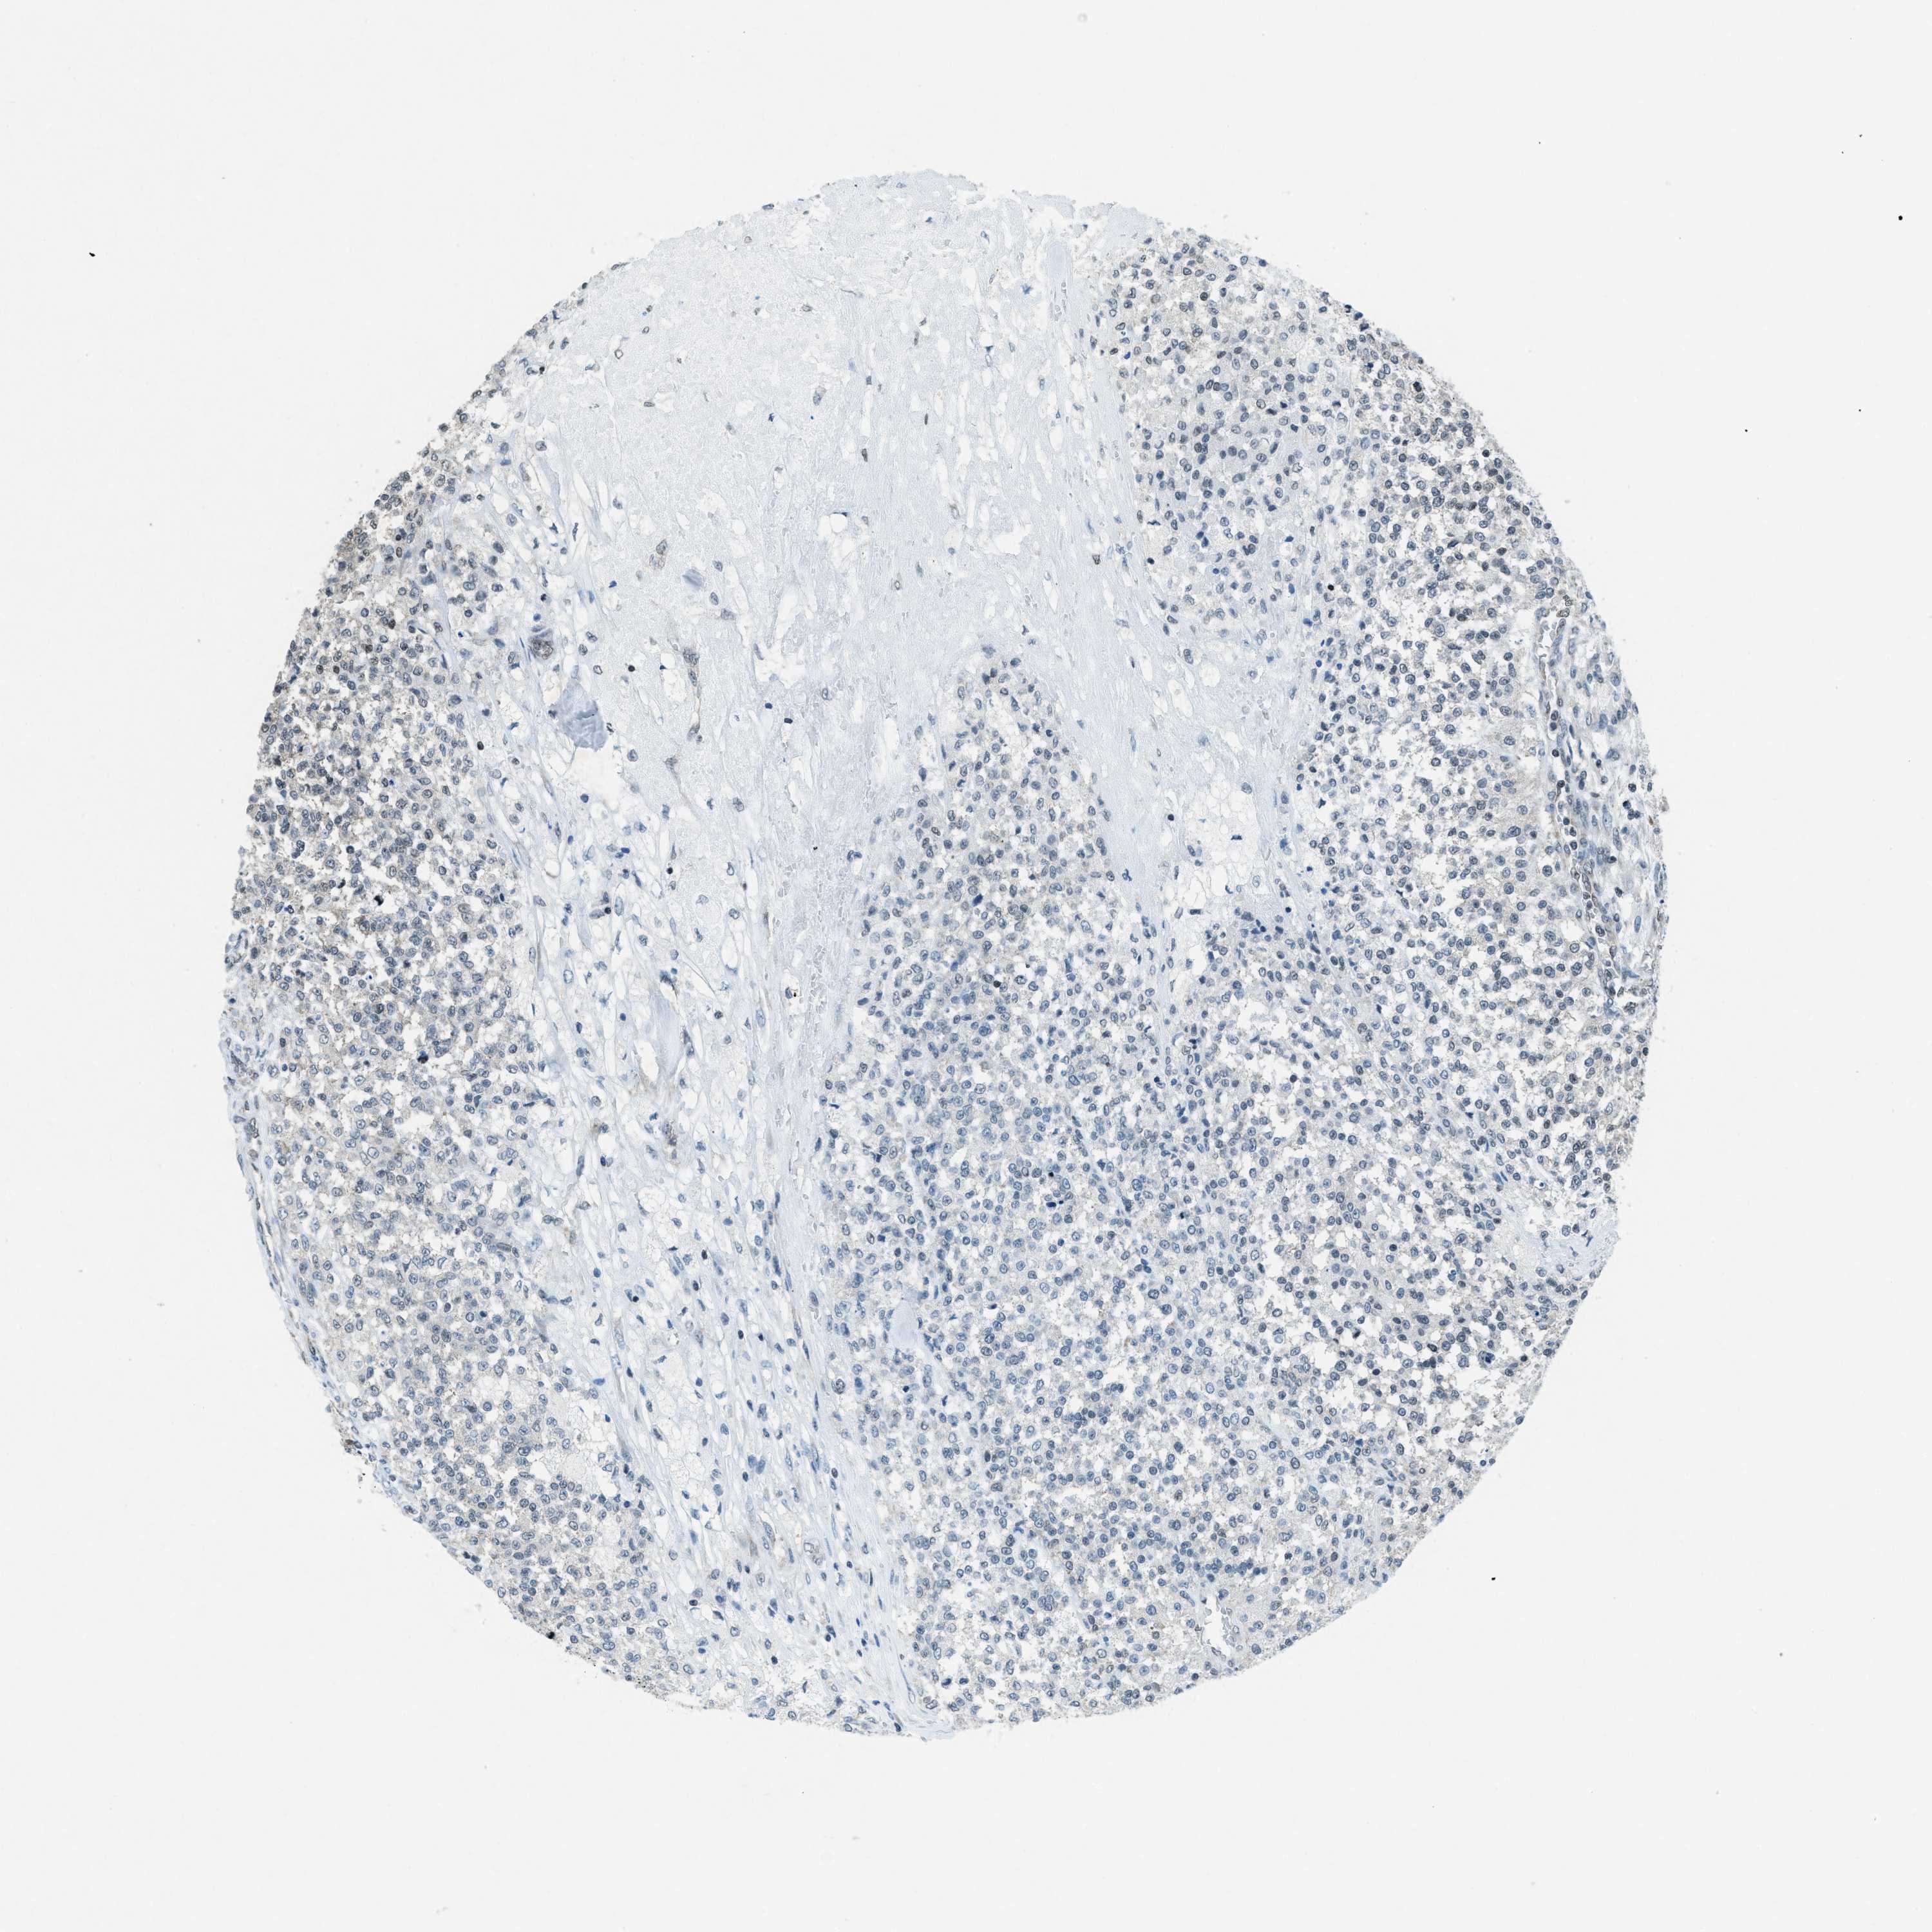

TESTIS CANCER - Protein expressioni

A mouse-over function shows sample information and annotation data. Click on an image to view it in a full screen mode. Samples can be filtered based on level of antibody staining by selecting one or several of the following categories: high, medium, low and not detected. The assay and annotation is described here.

Note that samples used for immunohistochemistry by the Human Protein Atlas do not correspond to samples in the TCGA dataset.

Antibody stainingi

Antibody staining in the annotated cell types in the current human tissue is reported as not detected, low, medium, or high, based on conventional immunohistochemistry profiling in selected tissues. This score is based on the combination of the staining intensity and fraction of stained cells.

Each image is clickable and will lead to virtual microscopy that enables deeper exploration of all samples and also displays staining intensity scores, fraction scores and subcellular localization as well as patient and tissue information for each sample.

Antibody HPA061593

Antibody CAB016327

Seminoma, NOS

Carcinoma, Embryonal, NOS